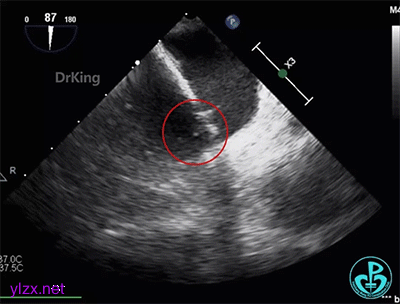

术前经食道超声描述:室间隔连续完整,房间隔中部菲薄,呈瘤样凸向右房面,基底宽约12mm,膨出约8mm。卵圆窝处薄弱,呈纤细线样回声,原发隔与继发隔间见纤细裂隙,入口约0.4mm,出口约0.8mm,卵圆瓣长约20.1mm,原发隔摆动幅度约13mm,继发隔厚约4.5mm,瓦式呼吸后,入口较宽约3.8mm,出口较宽约2.0mm,卵圆瓣左房侧末端迂曲。CDFI裂隙处可见微量左向右过隔血流信号。左心耳显示清楚,内未见异常回声。主动脉内中膜欠光滑,窦部宽约25mm,管腔未见明显狭窄与扩张,CDFI未见明显异常血流信号。各房室腔比例尚可,未见明显节段性室壁运动异常,各瓣膜形态、结构正常,启闭尚可。

超声诊断:先天性心脏病,卵圆孔未闭(长隧道型)。

右心声学造影检查:微泡造影剂经右肘正中静脉、上腔静脉进入右房,充盈良好,可见小楔形负性充盈区,患者瓦氏呼吸后见细小微气泡自裂隙处进入左房,约25~30个,一个裂隙位于卵圆孔入口处,一个位于卵圆孔出口处。